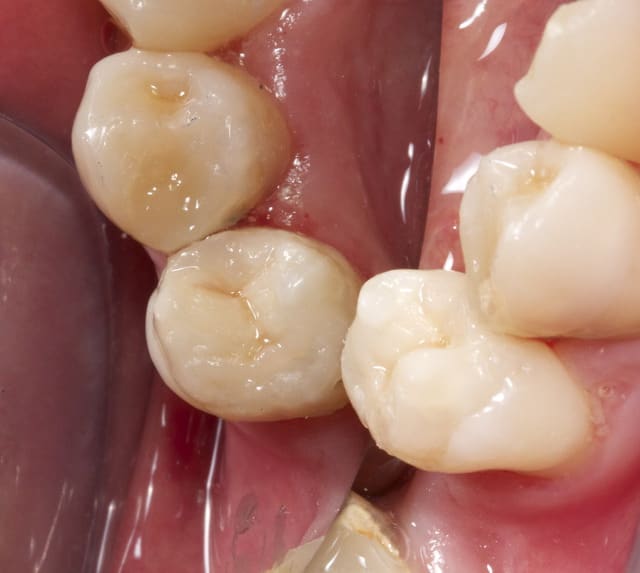

Apres obturation - fig.3,4

Apres 8 mois

Fig.5,6